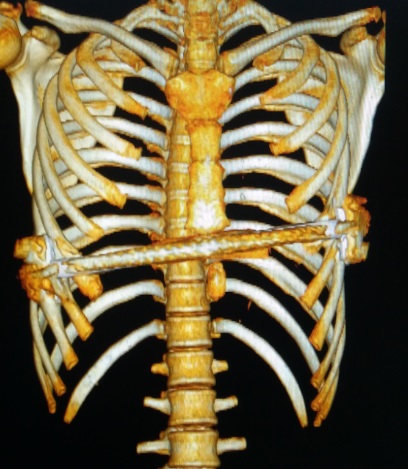

术前行X线检查:正位片提示胸壁内有钢板一条,钢板位置倾斜,脊柱轻度侧弯(图4)。侧位片提示前胸壁下部局部凹陷,钢板位置偏斜(图5)。行CT检查:可见胸壁内钢板影。横截面未见明显凹陷,但不同水平前后径明显不同(图6-10)。三维重建提示钢板影,前胸壁凹陷畸形(图11,12,13)。心电图及腹部超声检查未发现异常。

图11,骨性结构三维重建图:钢板位置倾斜。